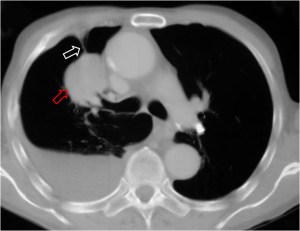

Imagen visible en la radiografía de tórax y en la TC que consiste en una banda radiodensa (flecha blanca) que desde un nódulo pulmonar (flecha roja) se extiende hasta la superficie pleural, en donde a menudo existe un engrosamiento focal. Este signo, descrito inicialmente como signo de malignidad, no es 100 % específico.

La imagen corresponde a un paciente con carcinoma epidermoide de pulmón.